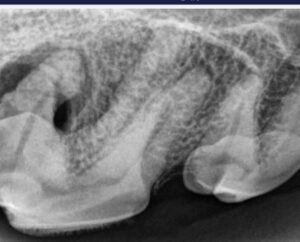

By Dr. Brook Niemiec

Let us share a little about Rypper, a VDS client and 9-year-old male German Shepherd.

Rypper is a classic example of why we must refrain from using the level of tartar to determine if a pet needs a dental procedure. He presented with mild tartar and gingivitis while being treated for a broken tooth. However, while under anesthesia, he was examined and radiographs taken, revealing severe periodontal disease to the distal (back) root.

Periodontitis represents a severe infection that was likely present for a long time and would’ve continued if Rypper had not been brought in for an unrelated matter. For these reasons, most veterinary dentists recommend annual cleanings regardless of outward evidence of disease. Especially in the case of Rypper, a German Shepherd and a breed not predisposed to gum disease, making this even more unexpected. Instead of treating periodontal disease, we advocate preventing it.

About Rypper’s tooth, extraction was a viable option, but because the front roots were healthy, we elected to section the tooth, extract the back root and perform a root canal on the front roots. This procedure saved half of the tooth and was far less invasive than extraction as the back root was easily removed.

Rypper recovered normally and, on recall the next day, was back to his normal self.